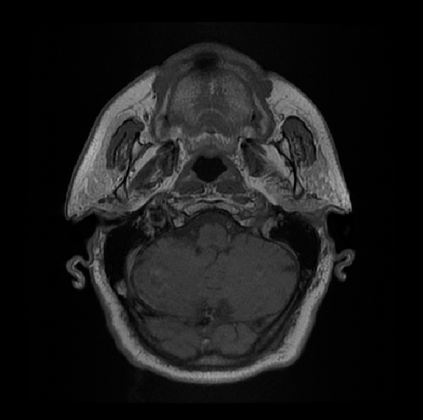

Organ at risk (OAR) segmentation is a critical process in radiotherapy treatment planning such as head and neck tumors. Nevertheless, in clinical practice, radiation oncologists predominantly perform OAR segmentations manually on CT scans. This manual process is highly time-consuming and expensive, limiting the number of patients who can receive timely radiotherapy. Additionally, CT scans offer lower soft-tissue contrast compared to MRI. Despite MRI providing superior soft-tissue visualization, its time-consuming nature makes it infeasible for real-time treatment planning. To address these challenges, we propose a method called SegReg, which utilizes Elastic Symmetric Normalization for registering MRI to perform OAR segmentation. SegReg outperforms the CT-only baseline by 16.78% in mDSC and 18.77% in mIoU, showing that it effectively combines the geometric accuracy of CT with the superior soft-tissue contrast of MRI, making accurate automated OAR segmentation for clinical practice become possible. See project website https://steve-zeyu-zhang.github.io/SegReg